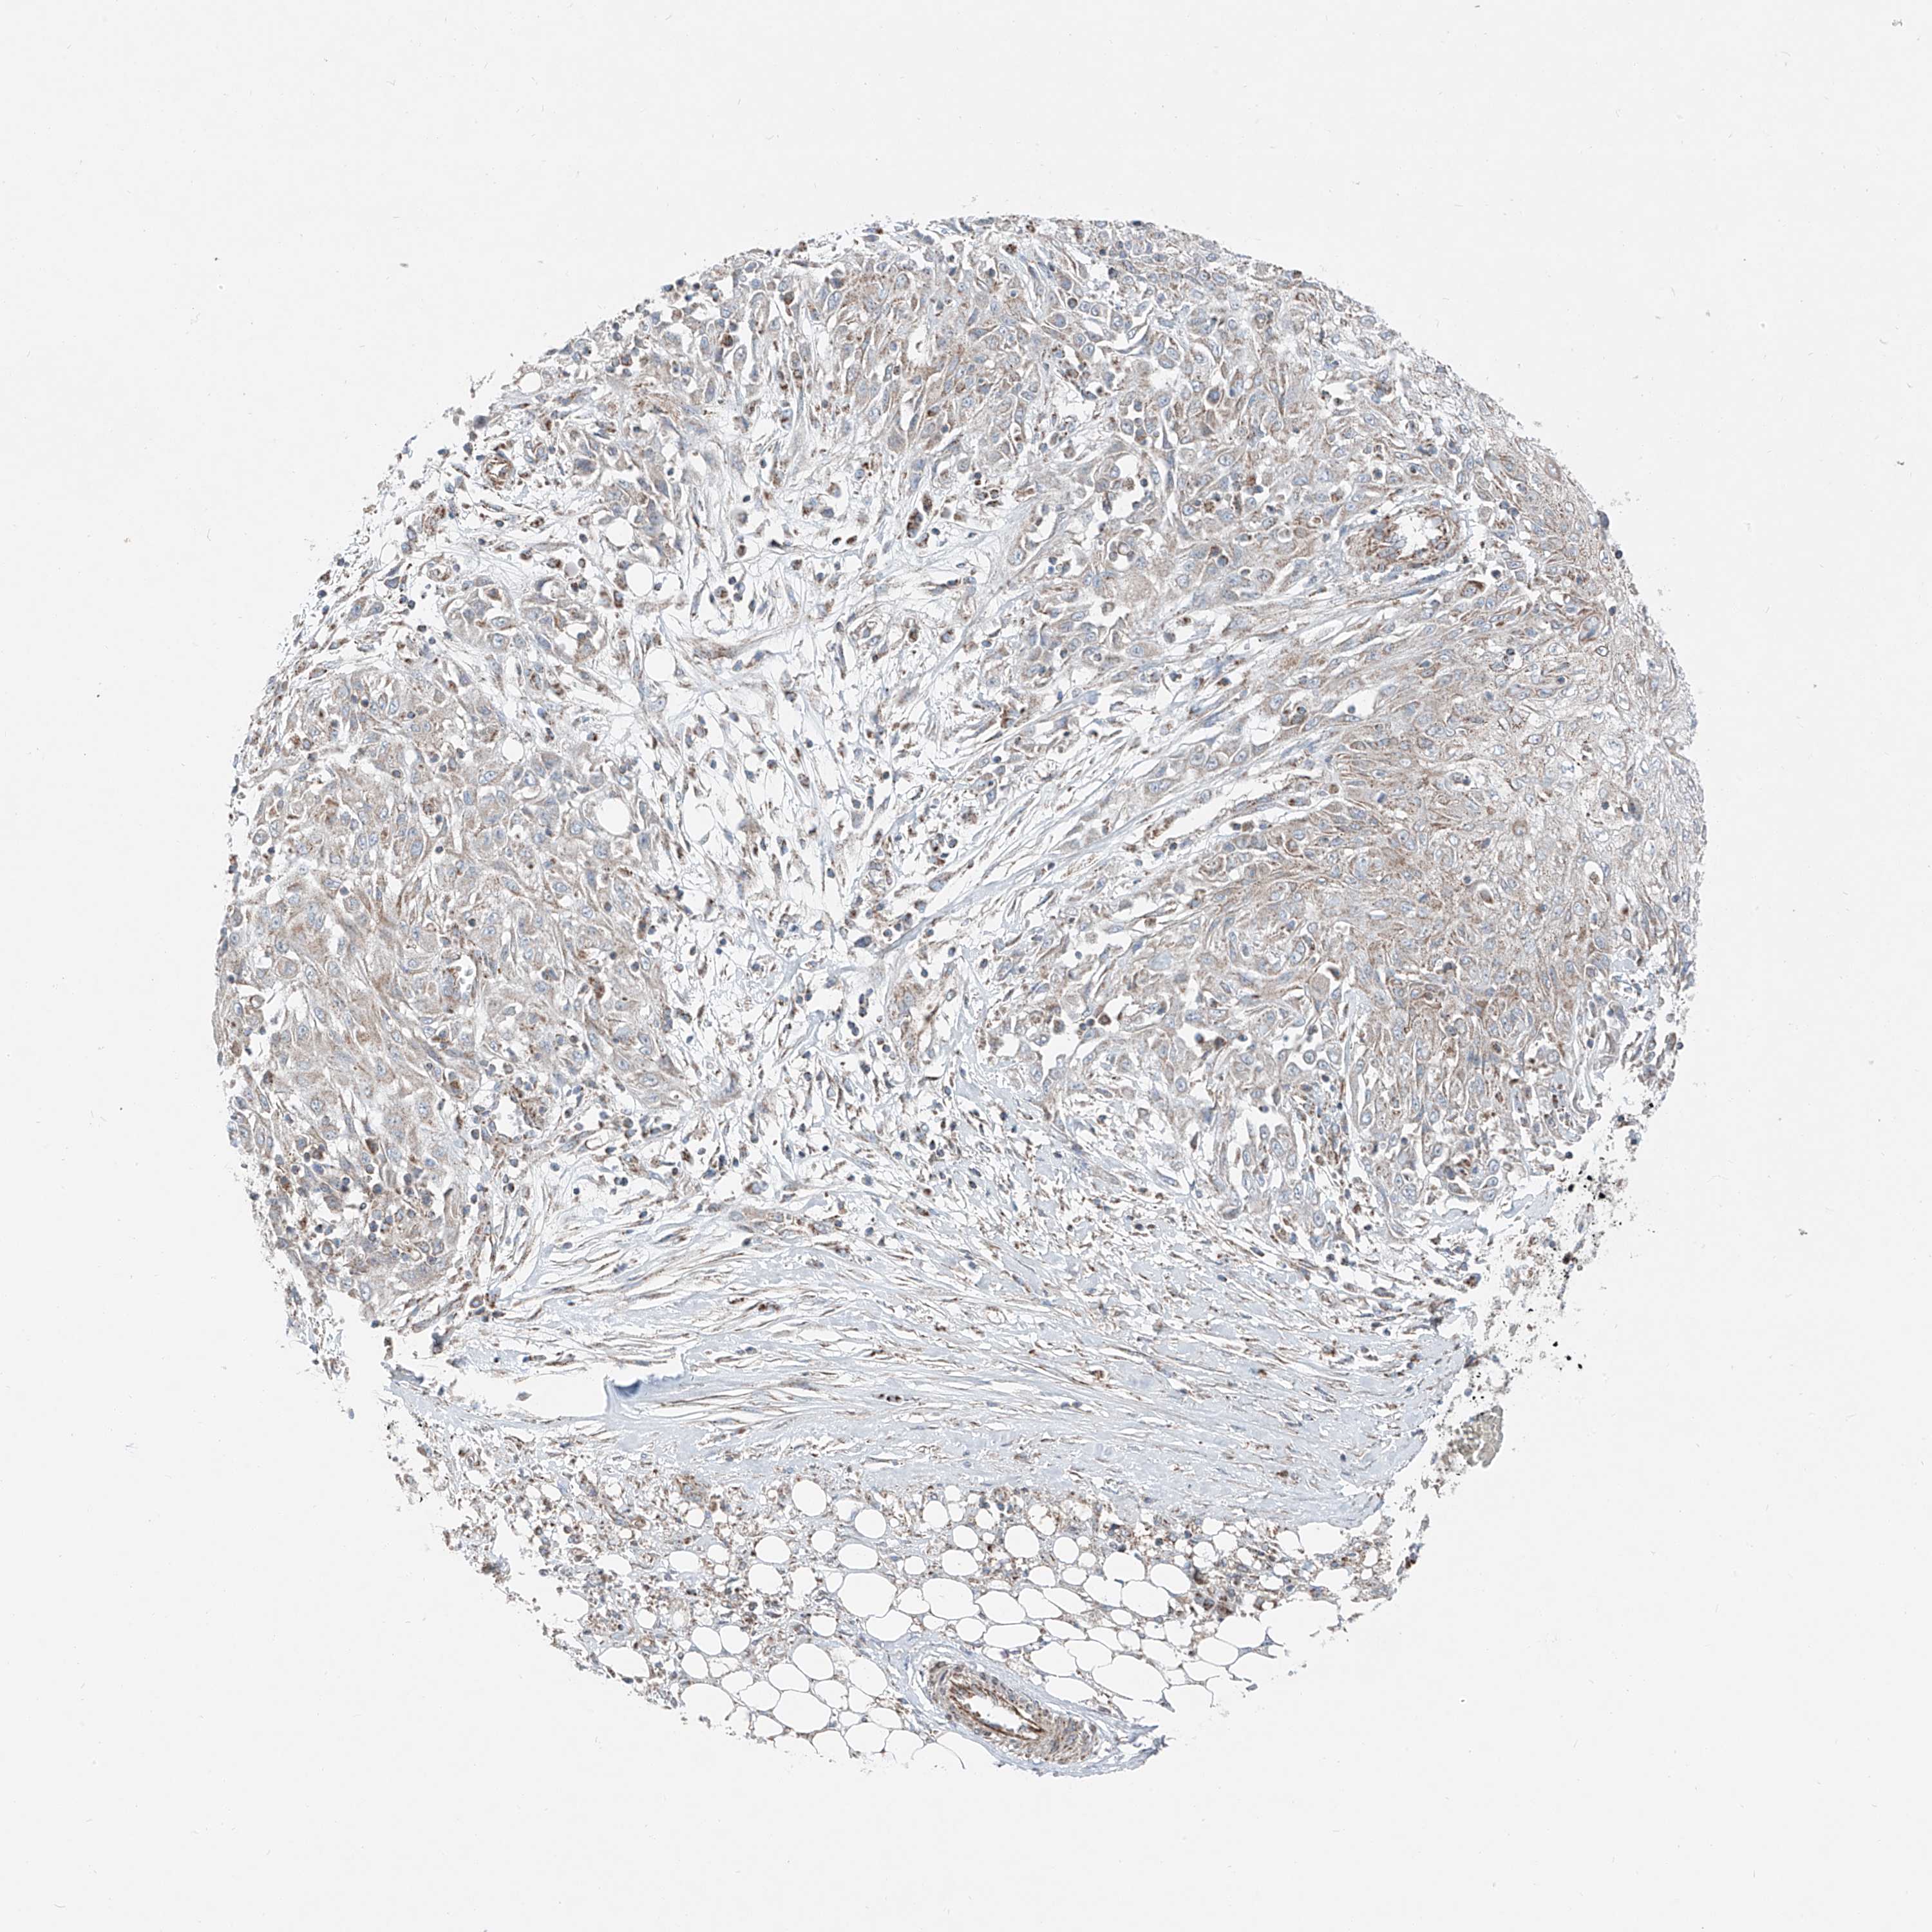

SKIN CANCER - Protein expressioni

A mouse-over function shows sample information and annotation data. Click on an image to view it in a full screen mode. Samples can be filtered based on level of antibody staining by selecting one or several of the following categories: high, medium, low and not detected. The assay and annotation is described here.

Antibody stainingi

Antibody staining in the annotated cell types in the current human tissue is reported as not detected, low, medium, or high, based on conventional immunohistochemistry profiling in selected tissues. This score is based on the combination of the staining intensity and fraction of stained cells.

Each image is clickable and will lead to virtual microscopy that enables deeper exploration of all samples and also displays staining intensity scores, fraction scores and subcellular localization as well as patient and tissue information for each sample.

Antibody HPA030316

Staining

High

Medium

Low

Not detected

Intensity

Strong

Moderate

Weak

Negative

Quantity

>75%

75%-25%

<25%

None

Location

Nuclear

Cytoplasmic/membranous

Cytoplasmic/membranous,nuclear

Basal cell carcinoma